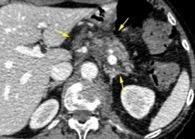

T. mixto de células germinales del testículo izquierdo

Nódulos pulmonares múltiples. (flechas verdes). Masas paratraqueales. (flechas amarillas). Dudoso ensanchamiento retrocrural (flechas negras). sigue….

Ttawfik A et al. Trans-diaphragmatic Pathologies: Anatomical Background and Spread of Disease on cross-sectional Imaging. Current Problems in Diagnostic Radiology. 2021.

T. mixto de células germinales del testículo

izquierdo Metástasis pulmonares. (flechas verdes). Ganglios paratraqueales. (flechas amarillas). Ganglios retroperitoneales (flechas negras)

Tawfik A et al. Trans-diaphragmatic Pathologies: Anatomical Background and Spread of Disease on cross-sectional Imaging. Current Problems in Diagnostic Radiology. 2021.